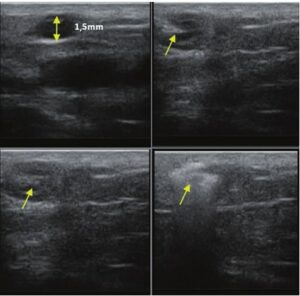

La ecografía Doppler permite obtener imágenes de grandes vasos y perforantes que suelen estar situados en las capas más profundas del tejido subcutáneo (fig. 1). Desgraciadamente, la ecografía convencional no es capaz de obtener imágenes de vasos más pequeños. Para visualizar los vasos más pequeños situados cerca de la superficie de la epidermis y en la capa superior del tejido subcutáneo, se utiliza el HFU (fig. 1). Gracias al uso de transductores con frecuencias superiores a 20 MHz, se obtiene una imagen ecográfica de alta resolución en la que podemos diferenciar estructuras menores de 0,1 mm. Sin embargo, cuanto mayor es la resolución, menor es la penetración del haz de ultrasonidos en las capas de la piel. Por lo tanto, dependiendo del transductor y del aparato, es posible penetrar en la piel hasta una profundidad de 20-30 mm como máximo. Tal penetración, junto con la alta resolución de la imagen, permite la evaluación incluso de vasos sanguíneos muy pequeños (fig. 2). Durante el examen con el uso de transductores de alta frecuencia, se puede evaluar con precisión el curso y la ubicación de los pequeños vasos en la piel. Esto es particularmente relevante para la selección del método de cierre del vaso y la planificación del procedimiento ya que, en la práctica, la superficie de la piel muestra muy a menudo únicamente un pequeño número de vasos o un ligero fragmento de un vaso; solo tras el examen por ecografía podemos determinar su número y curso reales. Para un cierre eficaz del vaso, es necesario hacerlo en toda su longitud. No debe limitarse al fragmento visto «a simple vista» en la superficie de la piel, ya que el cierre del fragmento causará su rápida recanalización(7). Con frecuencia, el vaso visible en la superficie de la piel cambia su curso, se vuelve más tortuoso y se desplaza a las capas más profundas de la piel(8). Por lo tanto, el curso de la vena y las perforantes deben conocerse y determinarse bien antes del procedimiento. El HFU también permite obtener imágenes de las perforantes entre pequeños vasos. Además, aparte de la evaluación del curso y la anatomía, la imagen ecográfica, gracias al software de ultrasonidos, también permite determinar los parámetros básicos como el diámetro del vaso, el grosor de su pared, la profundidad en la piel así como la presencia o ausencia de perfusión en el interior del vaso(6) (fig. 3). Gracias al transductor electrónico multielemento con la frecuencia de 40 MHz introducido en el mercado por Ultrasonix, también es posible visualizar la perfusión en los vasos en el modo Doppler color (fig. 4).